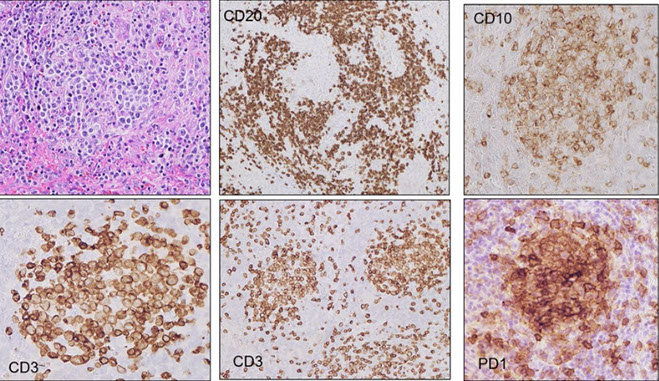

Angioimmunoblastic T-cell lymphoma and other nodal lymphomas of T follicular helper (TFH) cell origin

- Angioimmunoblastic T-cell lymphoma

- Follicular T-cell lymphoma